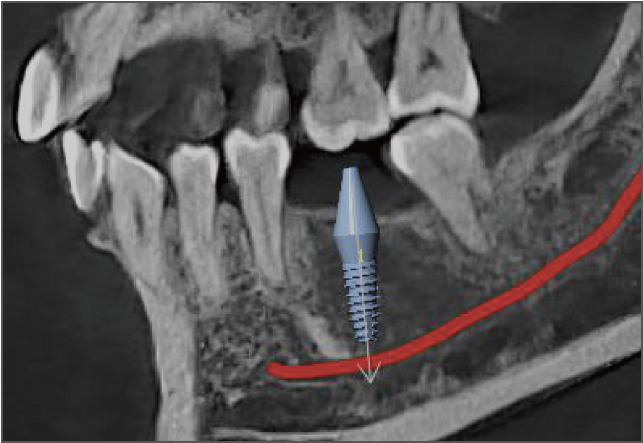

医疗机构内的医生可以将有疑惑的病灶定位保存,远程专家打开阅片软件后可快速定位到指定的位置进行分析。

AI 加持,事半功倍 兰台医令的阅片软件包含 AI 神经管绘制、AI 气道分析、AI TMJ分析、AI 牙弓曲线、AI 正畸头影测量等智能图像处理功能,可大大提高诊断效率,实现更好的医患沟通,让医生事半功倍。